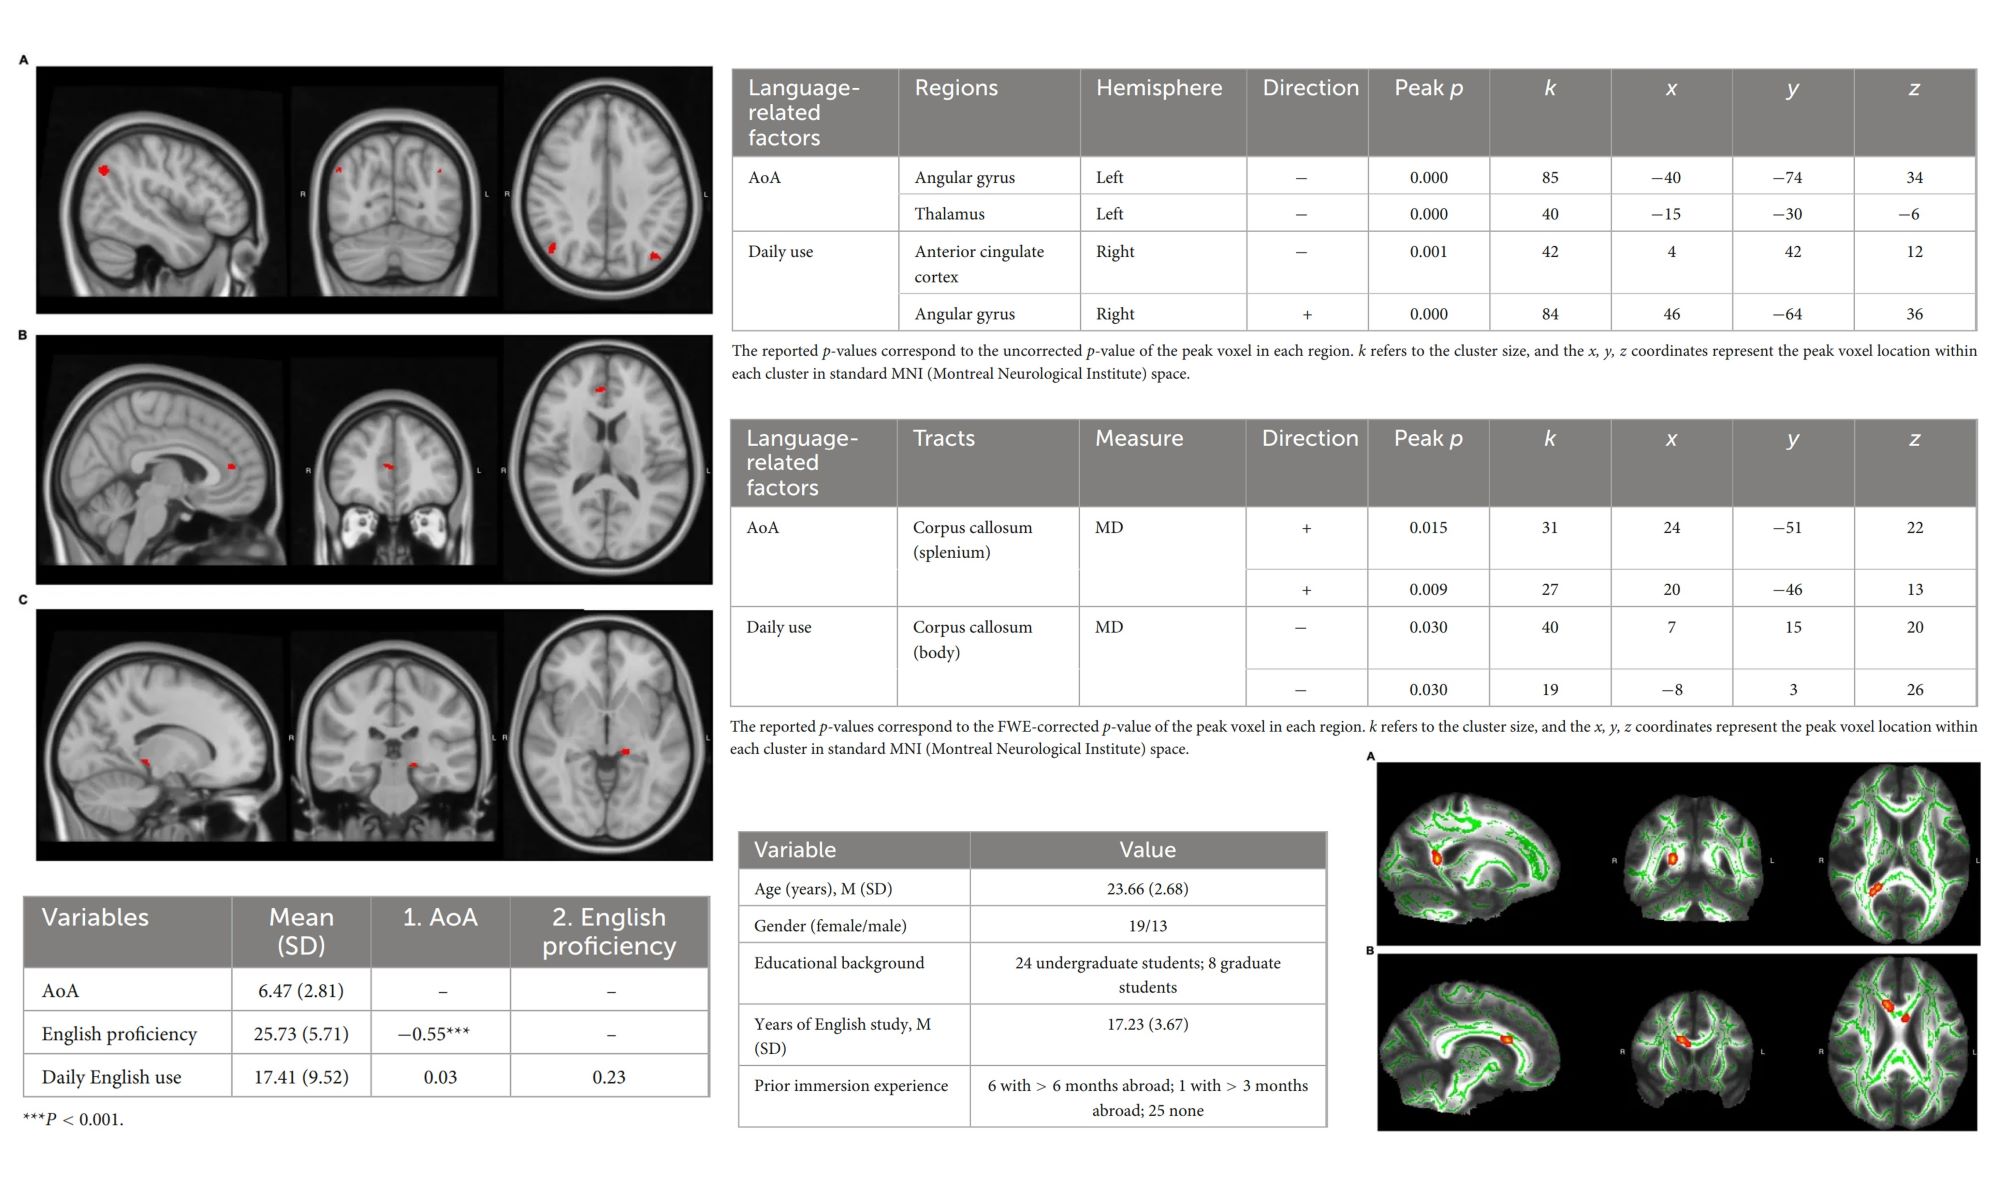

132. Brain structure correlates of foreign language learning experiences Xiaoqiao Wang, Jae-Yoon Kim, Jun-Ho Kim, Yoonseok Choi, Eun-Gyu Ha, Dong-Hyun Kim, Sunhae Sul, Sujin Yang, Hyun-joo Song Frontiers in Human Neuroscience. 2025, 19 https://doi.org/10.3389/fnhum.2025.1663218